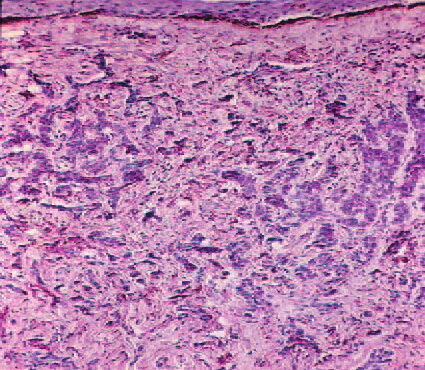

Bacillary angiomatosis = الورام الوعائي العصوي BACILLARY ANGIOMATOSIS Epidemiology BA is most commonly seen in patients with acquired immunodeficiency syndrome (AIDS) and a CD4 count less than 50 cells/mm3, with an incidence of 1.2 cases per 1000 at-risk patients Patients with other forms of immunosuppression, including patients with leukemia and recipients of organ […]